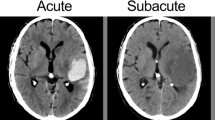

Two trained vascular neurologists (CHY and KYS) who were anonymized to the clinical information and prognosis independently reviewed NCCT scans after the initial training session of 100 patients external to our analysis. Qualitative NCCT markers of HE (heterogeneous density, black hole sign, blend sign, irregular shape, island sign, and satellite sign) were identified with a visual inspection (Fig. 1). Hematomas with heterogenous density and irregular shape were investigated on the axial NCCT slice that showed the largest hematoma area, according to the shape and density scales suggested by Barras et al. [3, 9] The density and shape scales are two separate 5-point categorical scales, and each scales range from category 1 (regular in shape scale and homogenous in density scale) to category 5 (irregular in shape scale and heterogenous in density scale). Heterogenous density and irregular shape was defined as shape and density scale of category 3, 4, or 5. Hematomas with heterogenous density and irregular shape were defined as shape and density scale of III, IV, or V on the axial NCCT slice showing the largest hematoma area as Barras et al. suggested [3, 9]. Black hole sign was defined as relatively hypoattenuated lesion, with a density difference at least 28 Hounsfield units (HU) compared with surrounding hematoma [20]. The definition of blend sign was coexistence of well demarcated hypodensity lesion and hyperdensity lesion with density difference of more than 18 HU [10]. Island sign was referred to as the presence of ≥ 3 small hematomas completely separated or ≥ 4 small hematomas partly separated from the main hematoma [11]. Satellite sign was defined as small hematoma (≤ 10 mm) separated from the main hematoma, with distance of 1 to 20 mm on at least one slice of the NCCT scan [21]. Discrepancies between the two readers (17 heterogenous densities, 7 black hole signs, 19 blend signs, 31 irregular shapes, 35 island signs, and 27 satellite signs) were adjudicated by joint discussion until a consensus was reached.

Representative cases of small ICHs with or without NCCT markers. a ICH without any qualitative NCCT markers that expanded in follow-up CT scan after 2 h from the baseline scan. Baseline hematoma density (mean HU) was 51.7 HU. b ICH with heterogeneous densities (black arrows) that did not expand in follow-up CT scan after 21 h from the baseline scan. Baseline hematoma density (mean HU) was 55.0 HU. c ICH with satellite sign (black arrow), blend sign (dashed black arrow), and black hole sign (white arrow) that did not expand in follow-up CT scan after 23 h from the baseline scan. Baseline hematoma density (mean HU) was 58.4 HU. d ICH with irregular shape and island sign (black arrows) that did not expand in follow-up CT scan after 10 h from the baseline scan. Baseline hematoma density (mean HU) was 57.1 HU. CT, computed tomography, HU, Hounsfield unit, ICH, intracerebral hemorrhage, NCCT, noncontrast computed tomography

It is challenging to evaluate the density and shape of the hematoma on NCCT because of image noise, artifacts, and similar appearance of cerebral parenchyma. Moreover, the current spatial resolution of CT may not be appropriate for grading qualitative density markers precisely, especially in small ICHs. Quantitative density assessments of hematomas when measured semiautomatically, for example, hematoma density in our study, are expected to have good interrater and intrarater reliability and well predict HE, regardless of the size of ICH. Hematoma density is also known to reflect the efficiency of hemostasis within hematoma, as the CT attenuation of hematoma increases in hyperacute phase of bleeding when sufficient hemostasis occurs [24, 25]. This initial increment of CT attenuation largely depends on clot contraction, which is the final step of blood clot maturation. When bleeding occurs, platelets aggregate and build platelet–fibrin network to form the temporary seal [26]. Then, red blood cells embed within the platelet–fibrin network to form a clot [27]. Finally, clot contracts to enhance the local hemostasis. In this period, because of platelet-generated contractile force, serum is extruded and local concentration of red blood cells within the clot increases [28]. This phenomenon manifests as the increment of hematoma density on CT scan.